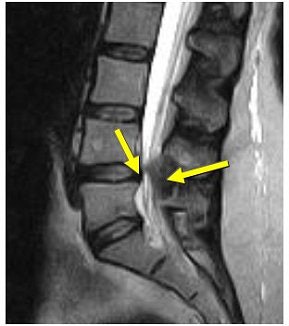

| Above, midsagittal T2-weighted MRI showed increase in stenosis at the L4 level by 2.0 mm with ventral thecal sac compression with axial loading (below). All images courtesy of Dr. Gerald Anzalone. |

Moreover, a number of studies have suggested that conventional MRI and CT are at considerable risk for failing to detect essential narrowing of the spinal canal when only the recumbent patient scanning position is utilized. This has been shown in patients with lumbar spinal pain combined with sciatica, radiculopathy, neurogenic claudication, or suspected lumbar spinal stenosis, according to research conducted by Dr. Jan Willen, Ph.D.; Dr. Barbro Danielson, Ph.D.; and colleagues at Sahlgrenska University Hospitals in Goteborg and Molndal, Sweden (Spine, December 1, 2001, Vol. 26:23, pp. 2607-2614; Acta Radiologica, November 1998, Vol. 39, 6, pp. 604-611; Spine, December 15, 1997, Vol. 22:24, pp. 2968-2976).

Willen and Danielson have also shown that axial-loaded imaging, during recumbent MRI or CT, simulates weight-bearing forces in the lumbar spine, provoking narrowing of the central spinal canal and neural foramina, and increasing the diagnostic accuracy of dynamic spinal stenosis. Dynamic stenosis has been defined in literature as a change in the cross-sectional dural sac area of greater than 15 mm² resulting in a decrease in the dural sac area to less than 75 mm (Spine, December 1, 2001, Vol. 26:23, pp. 2607-2614; Acta Radiologica, November 1998, Vol. 39, 6, pp. 604-611; Spine, December 1, 2001, Vol. 26:23, pp. 2601-2606).